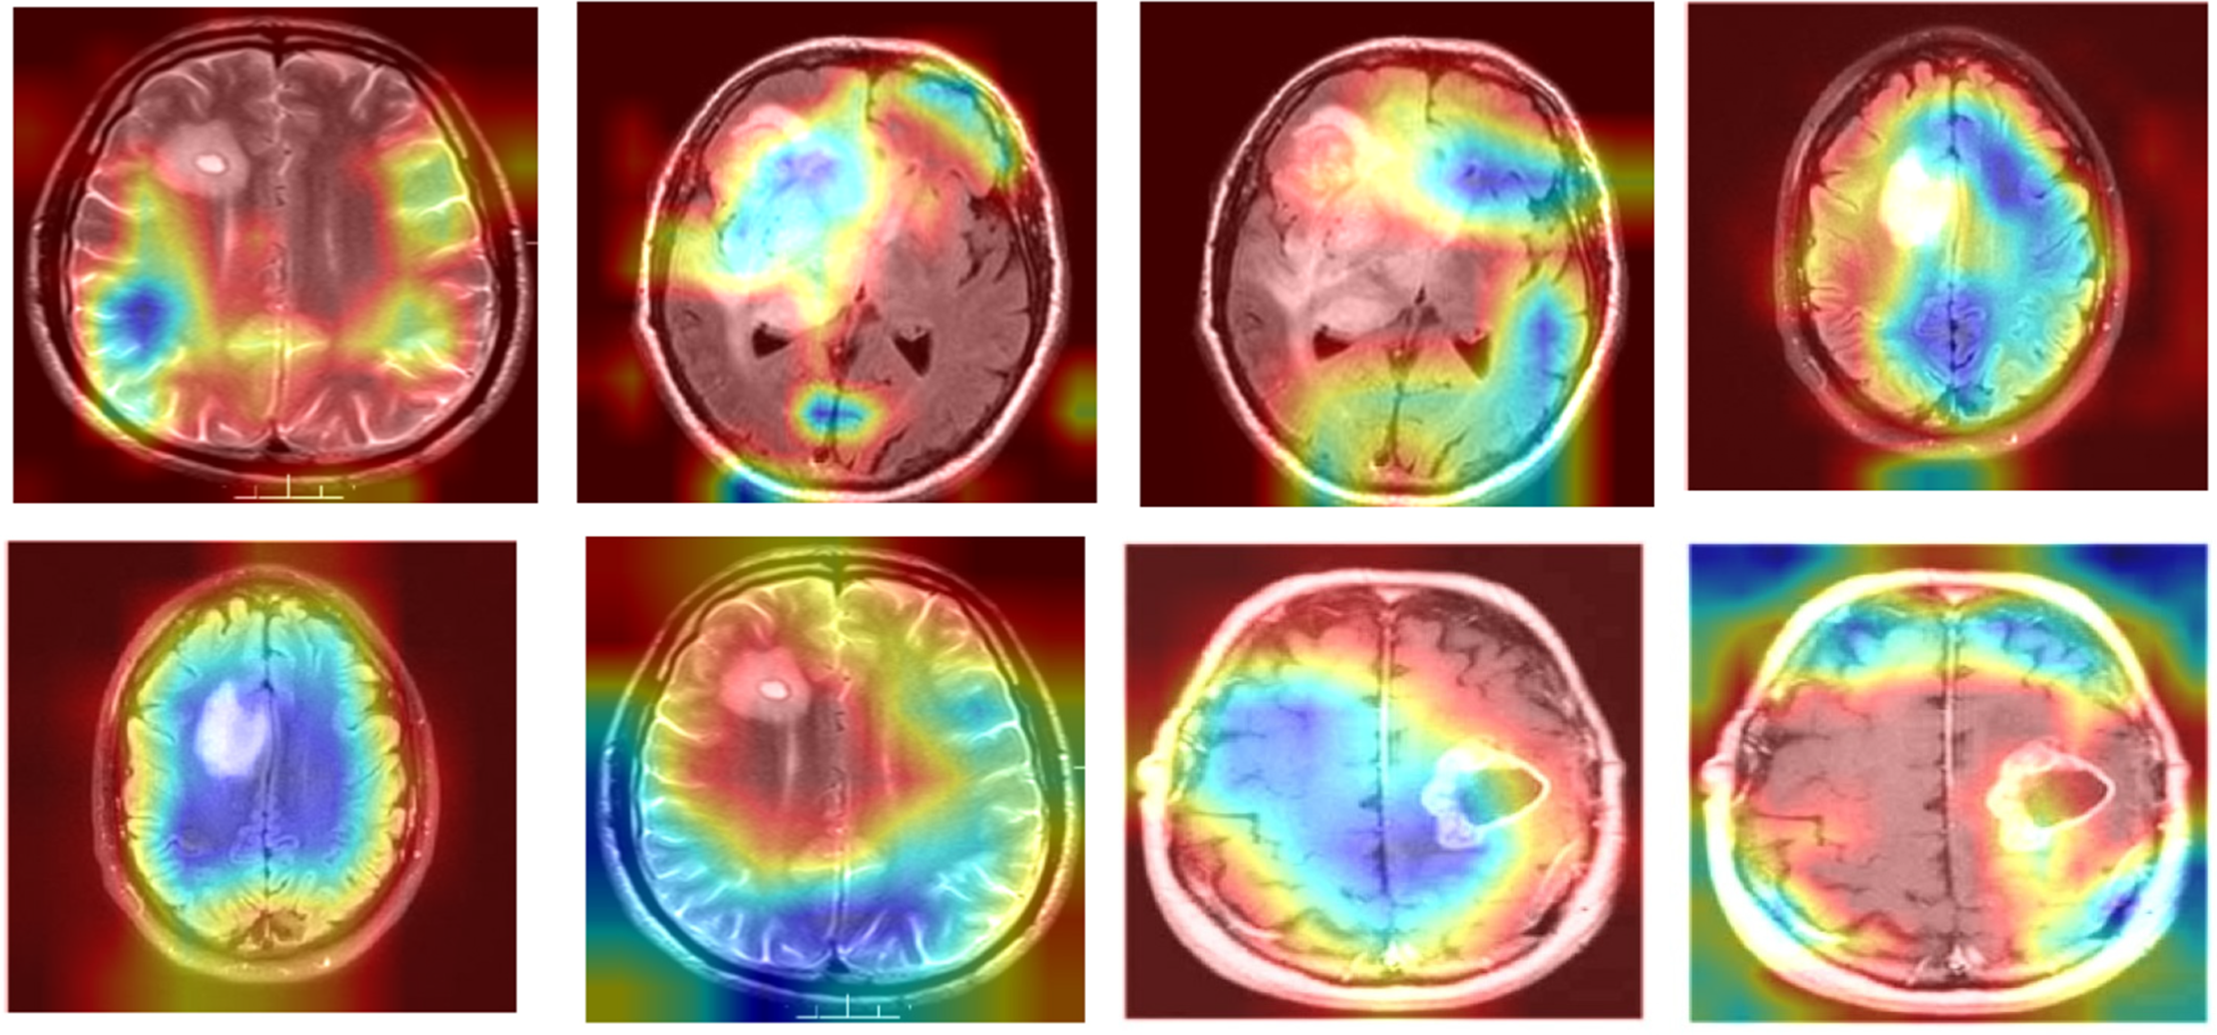

To visually demonstrate how the model processes and interprets MRI images, we present several Grad-CAM heatmaps, as shown in Fig. 6. A heatmap overlay on an MRI image, where the red-to-yellow gradient indicates areas of the highest importance, confirms that the tumor region is correctly identified. Fig. 7 illustrates the heatmaps generated by the basic CNN, the original DenseNet, and our modified DenseNet, highlighting the improved focus and clarity of our model. Fig. 8 shows a more detailed heatmap for MRI images, where tumors are not easily defined or are located in abnormal areas, illustrating how the model performs under stress.

Figure 7: Comparison of grad-CAM heatmaps across different models

Fig. 9 illustrates the working of the model to give focus on the tumor region, justifying its diagnostic ability. These Grad-CAM heat map zoning convincingly show that the model draws its predictions from relevant parts of the pattern suitable for diagnosis. It presents a simplified and comprehensible format through which the model’s actions can be easily explained to medical practitioners, thereby motivating clinical integration. Table 7 presents the results of an ablation study analyzing the impact of different architectural modifications on the DenseNet model’s performance.

Figure 9: Grad-CAM heatmap for modified DenseNet on MRI image